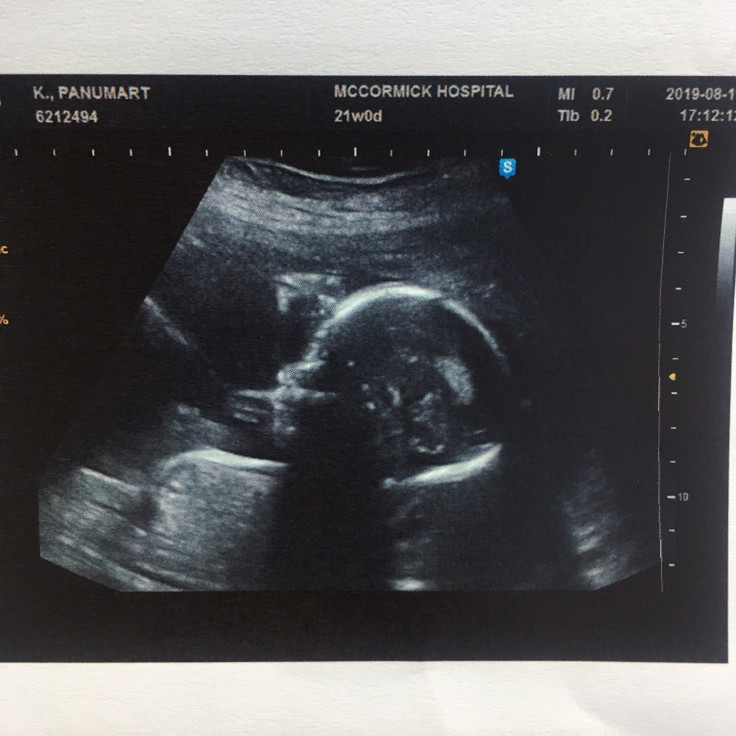

มีบ้านไหนซาวด์แล้วจมูกโด่งแบบนี้มั้ยคะ ออกมาจมูกน้องโด่งแบบนี้รึเปล่า? นี่คุณหมอบอกโด่งมาก?

โด่งจังเลยค่ะ